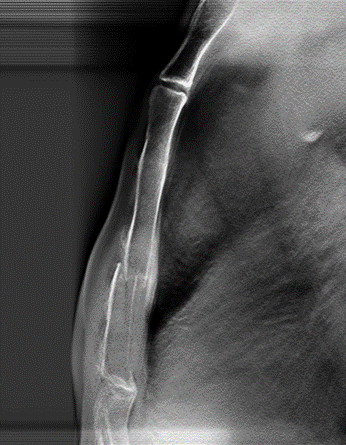

病例五:男,37歲。胸部外傷。

斷層融合能夠清晰顯示肋骨骨折。